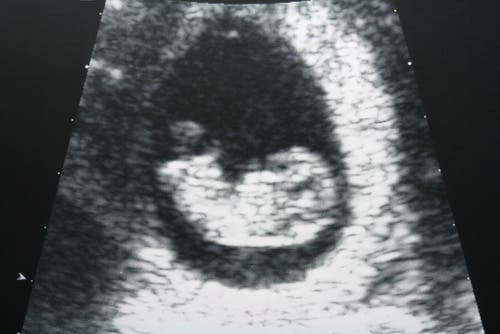

La ecografía es otra de las pruebas que se realizan para detectar posibles cambios en el útero y los ovarios.